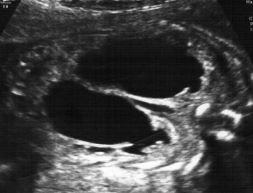

У всех детей предварительный диагноз был установлен антенатально во втором и подтвержден в третьем триместре беременности. По данным нашего анализа прогностическими являлись данные УЗИ в третьем триместре, которые и формировали прогноз постнатального ведения ребенка. Переднезадний диаметр (ПЗД) почечной лоханки составлял в среднем 29 мм (от 15,6 до 51 мм), толщина паренхимы – 3–5 мм (рис. 1), при этом у троих из четверых беременных отмечалось нормоводие. Это определило маршрутизацию беременных и позволило провести родоразрешение в специализированном стационаре с последующим переводом ребенка в отделение хирургии новорожденных для оказания срочной хирургической помощи.

Рис. 1. УЗИ почек плода на 34-й неделе гестации в В-режиме